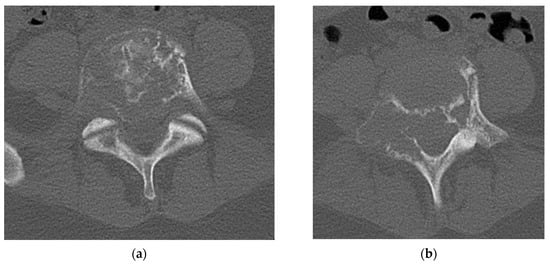

A CT scan of the lumbar spine provides a more detailed analysis of the bony remodeling which occurs during the formation of GCT. The “soap bubble” appearance seen on the plain radiograph is secondary to pseudotrabeculation, which can be appreciated on axial cuts of the CT scan [25]. The tumor itself closely resembles soft tissue density with no evidence of bony mineralization [27]. The cortex displays thinning or complete eradication, in which case there is an extension of the tumor into the surrounding soft tissue (Figure 2). A sclerotic border within the vertebral body is not uncommon (33%) and will be positioned opposite the eccentric distribution of the tumor. Shi et al. proposed that this unique appearance can be instrumental in the imaging diagnosis of a GCT [27].

Figure 2.

(a) Axial CT cuts of L5 vertebral body shows pseudotrabeculation of vertebral body with eccentric thinning of the right vertebral body cortex and formation of a contralateral sclerotic margin. (b) Bilateral pedicle involvement with near complete destruction of right sided L5 pedicle. (c) Sagittal cuts of L5 vertebral body shows loss of vertebral height indicating compression fracture with no retropulsion of bony elements. The lesion is seen to by lytic with cortical erosion especially in the posterior vertebral body. (d) Sagittal cut of L5 vertebral body demonstrates classic “soap bubble” imaging characteristic seen on the vertebral body of L5 on CT scan.